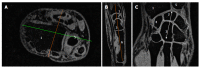

Methods: The study was conducted in 14 healthy volunteers (6 females and 8 males) between 30 and 58 years old and devoid of articular pain. Subjects were asked to lie down in the supine position with the right hand positioned above the pelvic region on top of a home-built rigid platform attached to the scanner bed. The wrist was wrapped with a flexible surface coil. MRI investigations were performed at 3T (Verio-Siemens) using volume interpolated breath hold examination (VIBE) and dual echo steady state (DESS) MRI sequences. Cartilage cross sectional area (CSA) was measured on a slice of interest selected from a 3D dataset of the entire carpus and metacarpal-phalangeal areas on the basis of anatomical criteria using conventional image processing radiology software. Cartilage cross-sectional areas between opposite bones in the carpal region were manually selected and quantified using a thresholding method.

Results: Cartilage CSA measurements performed on a selected predefined slice were 292.4 ± 39 mm(2) using the VIBE sequence and slightly lower, 270.4 ± 50.6 mm(2), with the DESS sequence. The inter (14.1%) and intra (2.4%) subject variability was similar for both MRI methods. The coefficients of variation computed for the repeated measurements were also comparable for the VIBE (2.4%) and the DESS (4.8%) sequences. The carpus length averaged over the group was 37.5 ± 2.8 mm with a 7.45% between-subjects coefficient of variation. Of note, wrist cartilage CSA measured with either the VIBE or the DESS sequences was linearly related to the carpal bone length. The variability between subjects was significantly reduced to 8.4% when the CSA was normalized with respect to the carpal bone length.